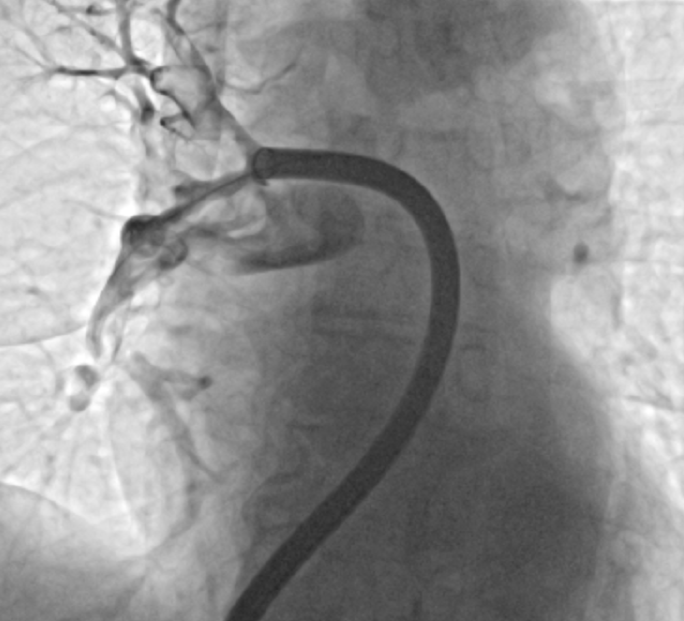

V Splošni bolnišnici Murska Sobota je bila opravljena prva uspešna mehanska odstranitev krvnega strdka iz pljučne arterije.

Zdravnik skozi večjo veno, običajno v dimljah, uvede cevko – kateter – in jo pod rentgenskim nadzorom vodi do mesta, kjer se nahaja strdek.

Nato s posebnim sistemom ustvari podtlak in strdek dobesedno »posesa« iz žile ali ga mehansko zajame in odstrani.